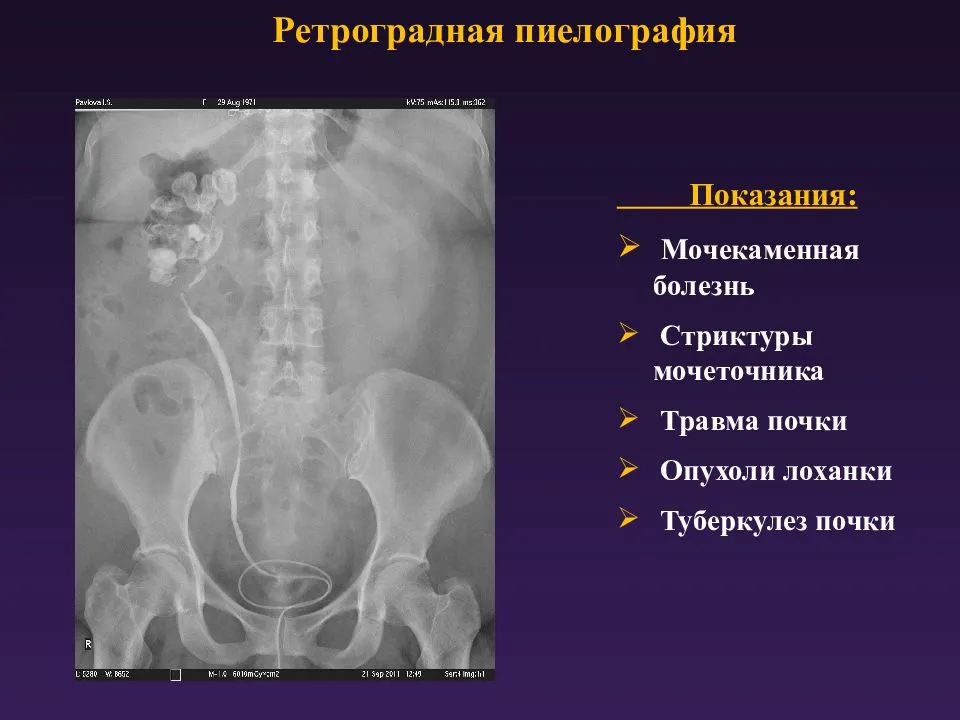

Изображения КТ конкрементов мочевого пузыря